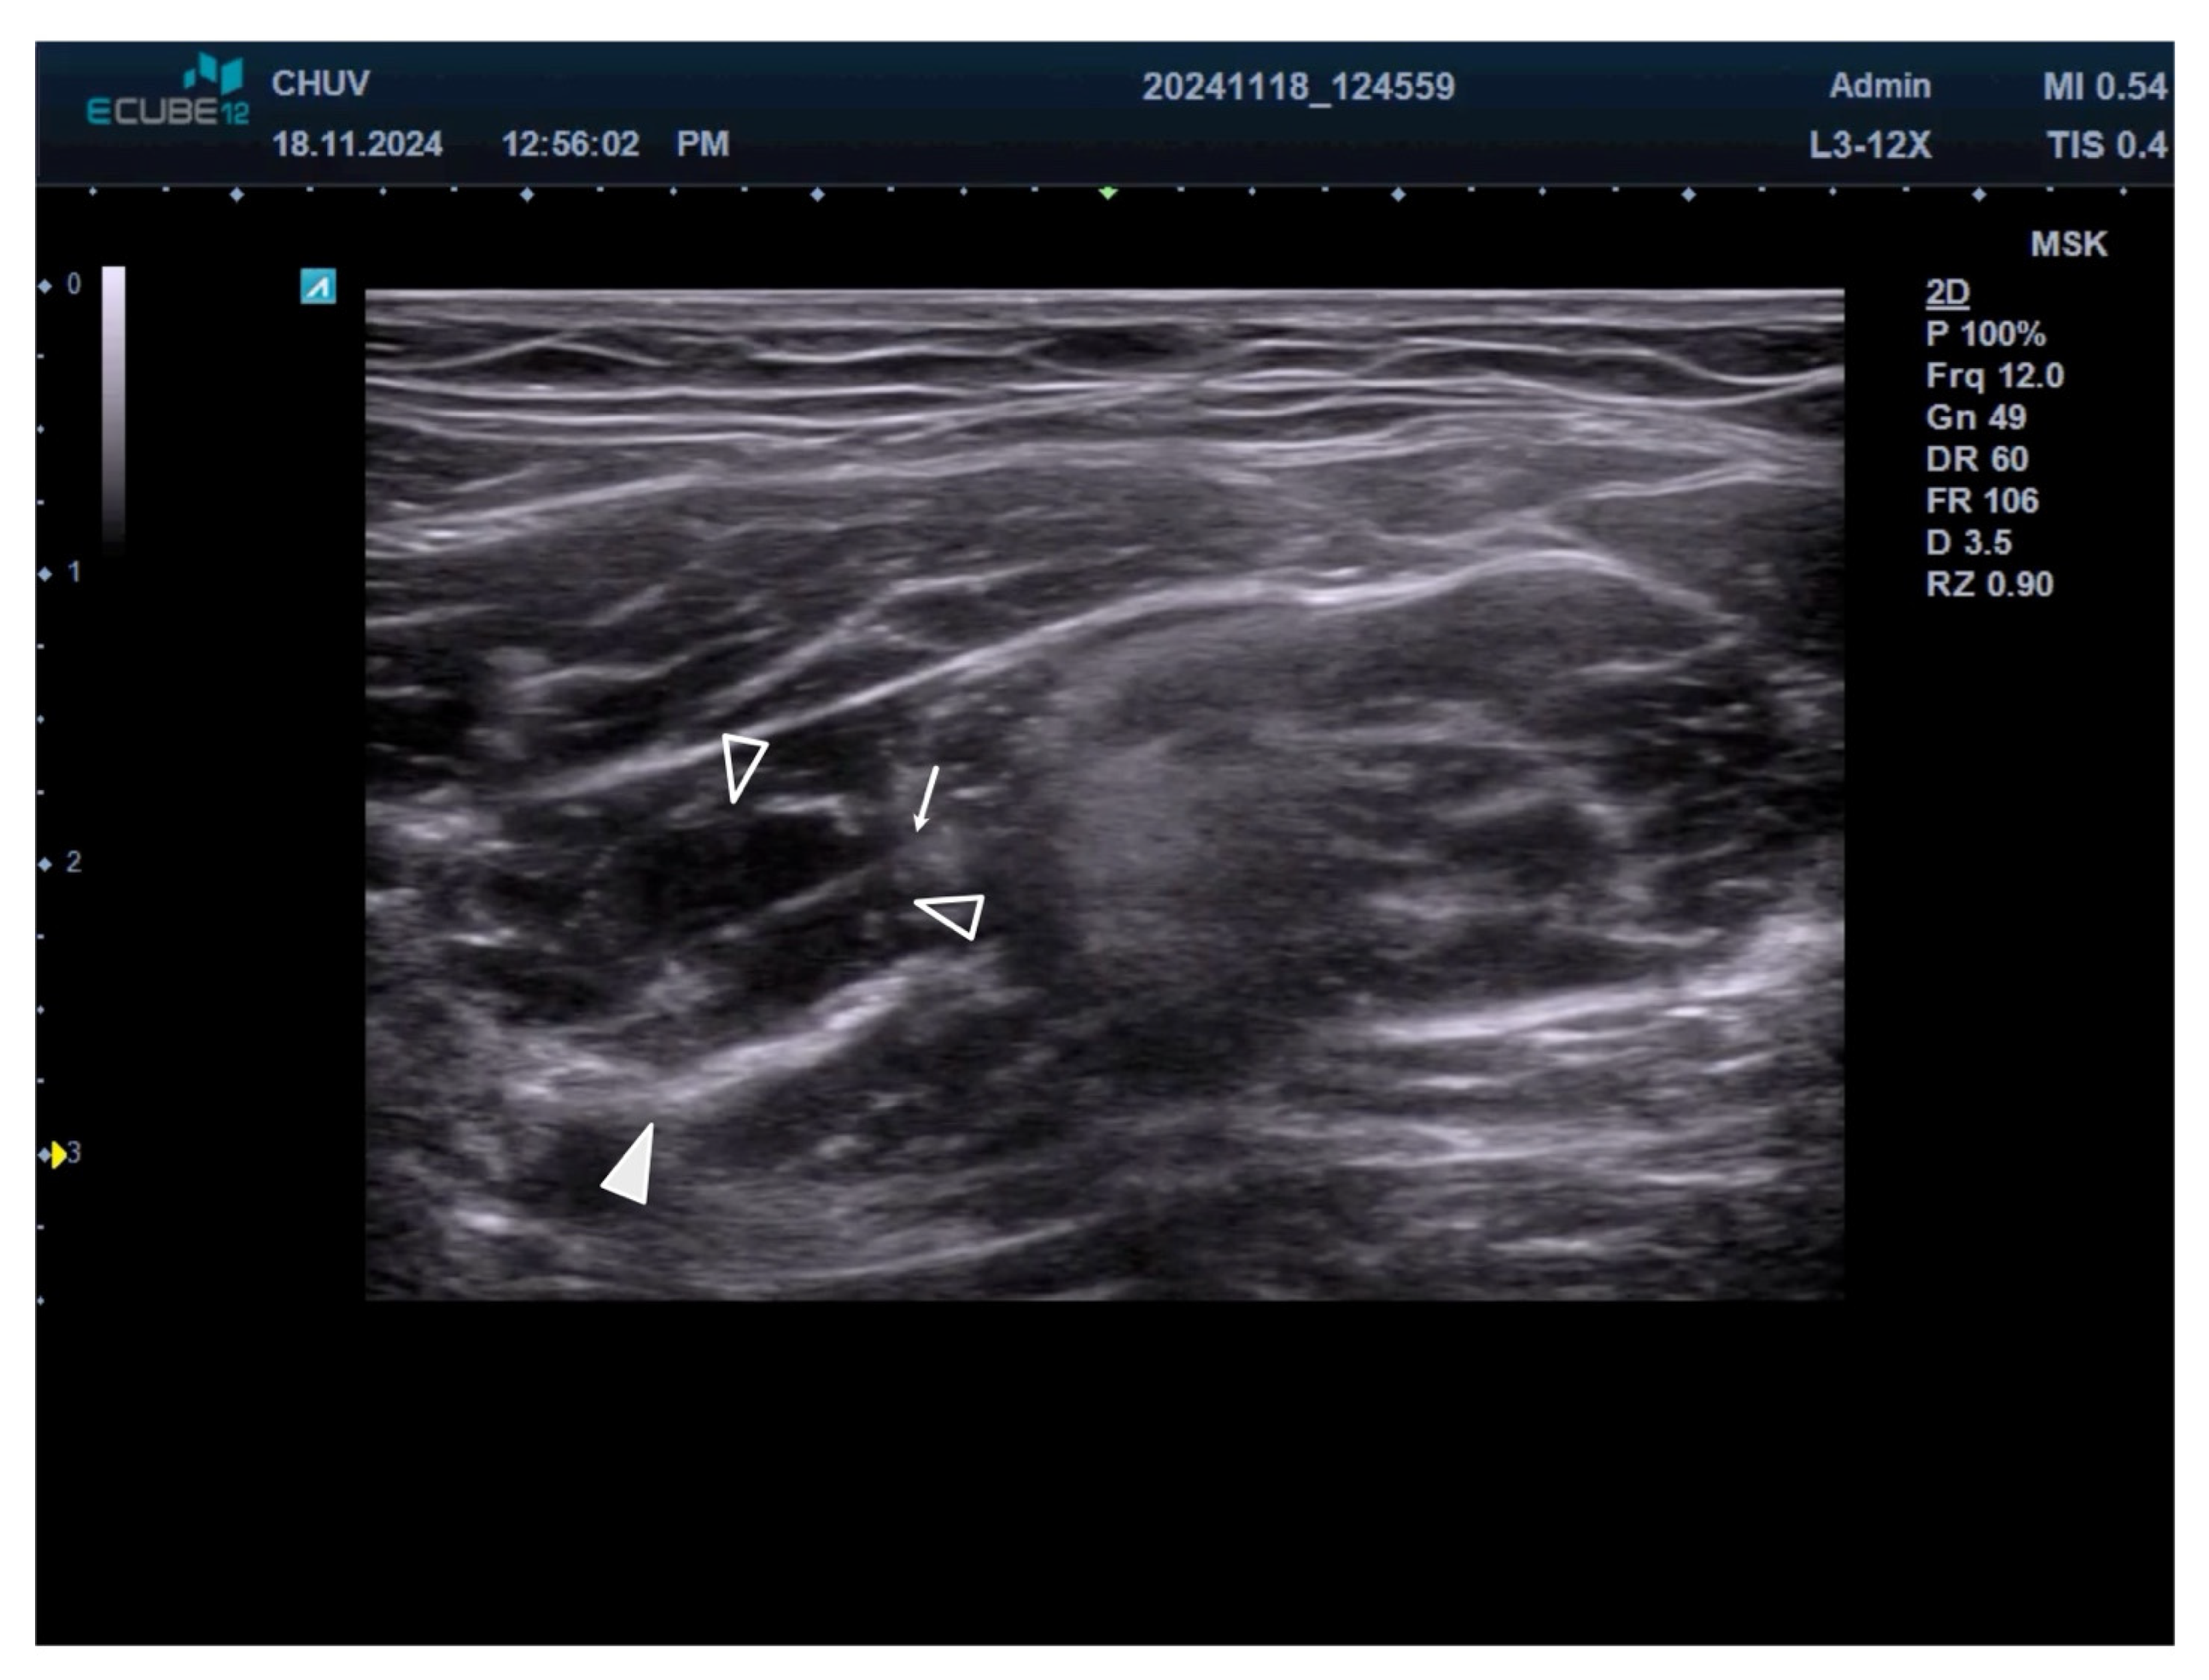

2.3. Motor Nerve Branch Identification

2.4. Injection Technique